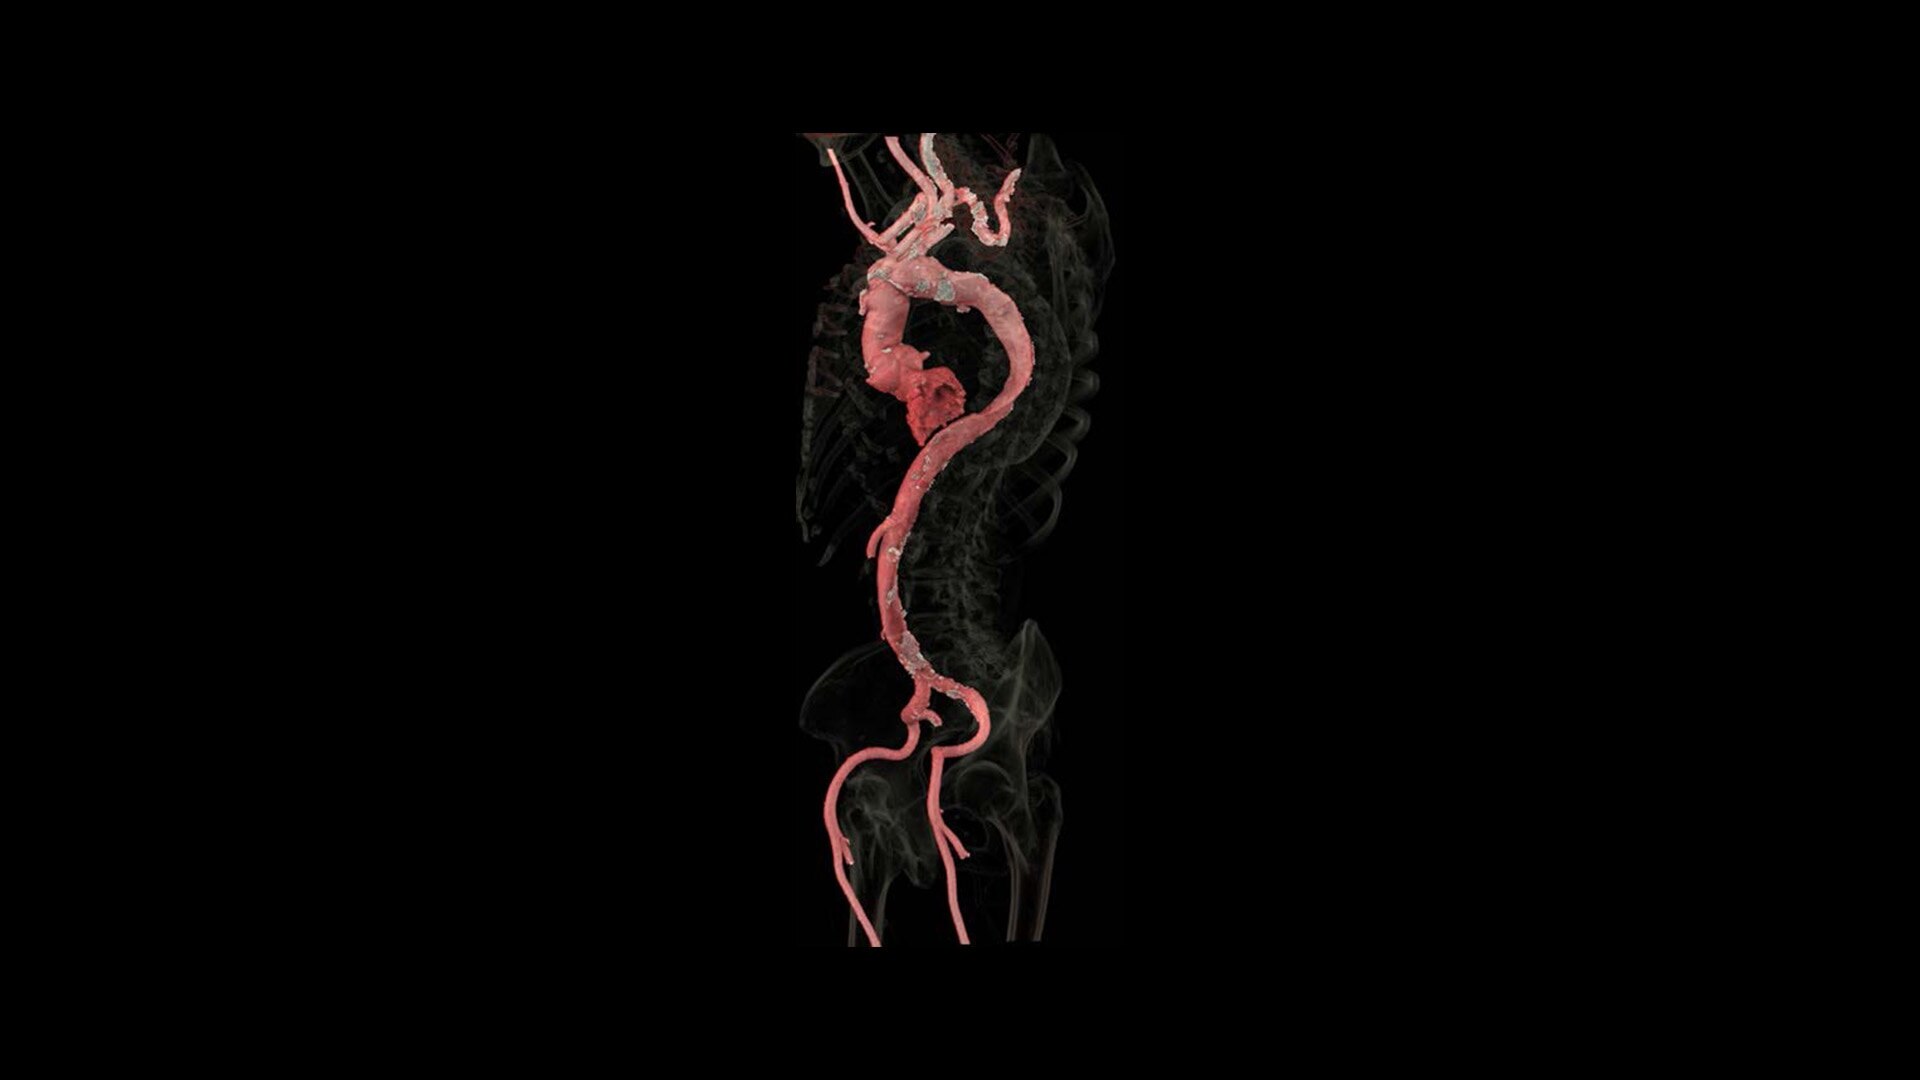

True Enhance DL

Designed to enhance what matters

True Enhance DL is a deep learning-based processing method intended for contrast enhancement of single energy images. True Enhance DL uses a dedicated Deep Neural Network (DNN) trained to estimate monochromatic, 50 keV GSI images from single-energy X-ray. This technology brings four deep learning models that the user can choose depending on different contrast enhancement phases by clinical tasks.